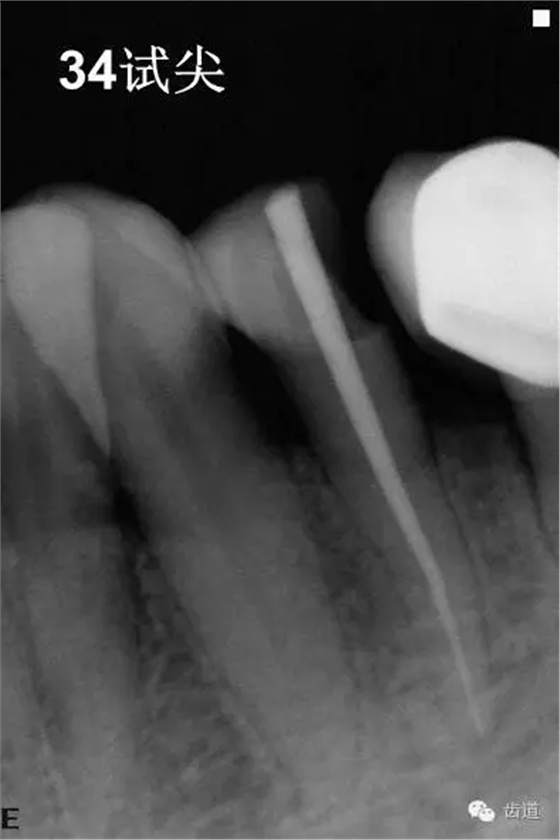

4、34常規(guī)根管治療。(2013年8月)

3、34術(shù)前片顯示遠(yuǎn)中面暗影近髓